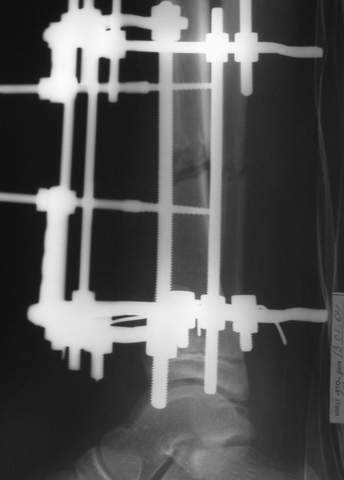

2

3a

3b

3c

В аттачте № 3 - один из примеров полукольцевого аппарат...

Это уже я баловался.

Итог? Работы больше (по времени и

интраоп "подгонке"), срастается также, а особого преимущества по сравнению с

"чиста" кольцевым (вес, удобство ношения и пр.) - я, по крайней мере,

не нашел.

Теперь не балуюсь.